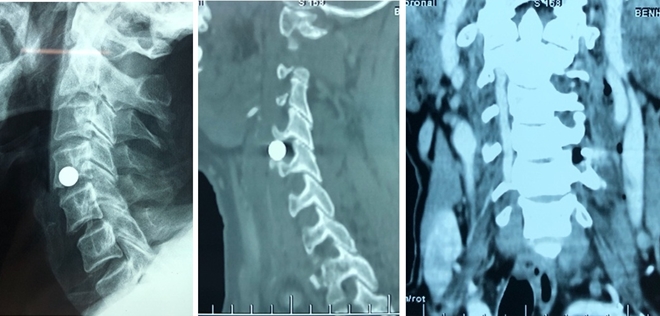

Hình ảnh viên đạn bi chèn đốt sống cổ bệnh nhân Biểu.

Khi nhập viện, bệnh nhân có vết thương nhỏ có đường kính 1cm nằm ở phía bên ngoài vùng cổ bên trái đoạn ngang thân sống C4-5, cảm giác chóng mặt; cơn đau lan từ vết thương đến mặt trước ngoài vùng vai và cánh tay bên trái, kèm theo đó là biểu hiện yếu động tác dạng vai và gập khuỷu.

Hội chẩn giữa các BS Khoa Phẫu thuật cột sống và Khoa Chẩn đoán hình ảnh thống nhất chẩn đoán: có ngoại vật bằng kim loại nằm mặt trước bên trái khoảng gian đốt sống C4-5; chèn vào lỗ liên hợp C4-5 bên trái gây tổn thương động mạch đốt sống và rễ thần kinh C5 bên trái. Bệnh nhân được chỉ định phẫu thuật cấp cứu lấy dị vật và xử trí tổn thương.

Sau 1 giờ phẫu thuật đã lấy ra được viên bi sắt đường kính 8 mm nằm cạnh bên trái của khí quản và thực quản; gây chèn ép động mạch đốt sống cổ và rễ thần kinh cổ C5 bên trái.